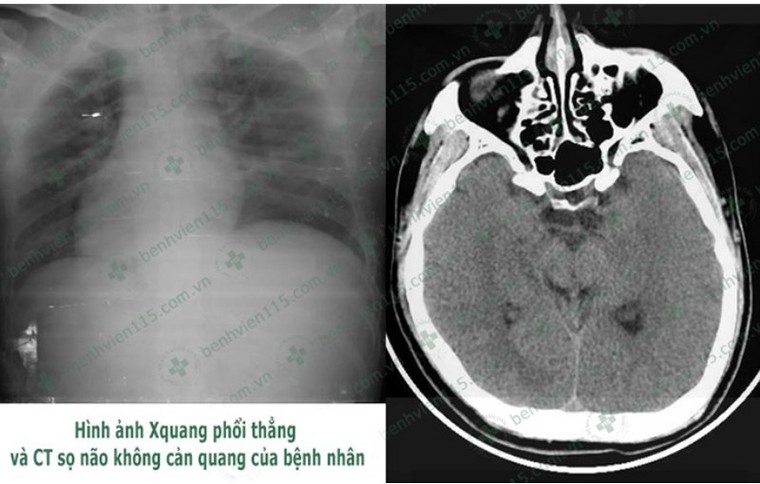

Tài xế hôn mê sâu khi lái xe chỉ vì quên ăn sáng ảnh 1

Kết quả chụp CT cho thấy anh N. bị hôn mê sâu. Ảnh: BV CUNG CẤP

Các BS chẩn đoán bệnh nhân N. hôn mê sâu do hạ đường huyết kéo dài và bị viêm phổi nặng. Bệnh nhân được hỗ trợ hô hấp bằng máy thở và truyền đường với nồng độ ưu trương để nâng mức đường huyết về bình thường. Tuy nhiên tri giác bệnh nhân vẫn không cải thiện. Các BS tiếp tục điều trị tích cực và tri giác bệnh nhân dần cải thiện. Sau một tuần điều trị, hiện bệnh nhân N. đã tỉnh táo hơn, có thể trò chuyện và nhận biết người thân nhưng rất chậm.